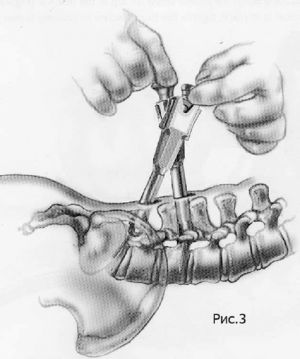

Хирургическое лечение спондилолистеза заключается в фиксации «разболтанных» позвонков титановыми винтами. Винты вводятся в позвонки через дужки позвонков (с лат. «педикули»), поэтому такая фиксация называется «транспедикулярной». Данный метод фиксации позвонков был впервые применен Roy-Camille в 1963г. и используется благодаря своей высокой эффективности по всему миру до настоящих дней.

Кроме того, в зависимости от техники проведения операции могут использоваться межтеловые кейджи. Кейдж (в переводе с английского «cage» означает «сетка») представляет собой титановый или пластиковый имплант, заполняемый собственной костной крошкой пациента или другим остеоиндуктивным (костьобразующим) материалом. Кейджи устанавливаются в полость диска, в результате чего восстанавливается высота последнего и соответственно высота фораминального отверстия (через который выходит спинномозговой корешок из позвоночного канала). Кейджи могут быть цилиндрической или прямоугольной формы, выполненными из титана или «PEEK»-керамики. Титановые цилиндрические кейджи в настоящее время используются редко.

Наиболее современным методом фиксации в настоящий момент является миниинвазивная технология введения винтов через небольшие разрезы. Этот метод позволяет меньше травмировать мышцы разгибатели позвоночника при введении винтов, а также более быстрому выздоровлению пациента и возвращению к обычному образу жизни, активному отдыху и работе. Технология данной фиксации заключается в использовании канюлированных винтов, т.е. винтов с отверстием в центре. В начале в тело позвонка вводится спица, а уже по спице вводится винт. Удаление грыжи диска и введение кейджа в межтеловой промежуток производится через тот же разрез, что и введение винтов.